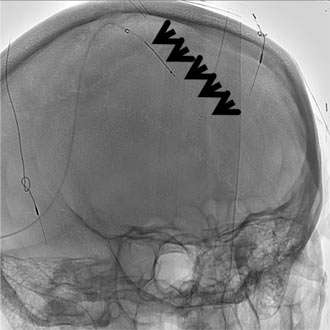

Sinus Thrombosis Figure 1: Normal

Figure 1: Normal

Cerebral venous sinus thrombosis is a rare condition when a large blood clot forms in a large vein in the brain called a dural venous sinus. The clot blocks the dural sinus and prevents the blood flow draining from the brain (Figure 1).

Brain imaging studies such as MRI and CT are commonly used to demonstrate the clot in the cerebral venous sinuses. If necessary, catheter angiography is also performed to visualize the relatively small clots or when catheter based clot-removing treatment is needed (Figure 1).